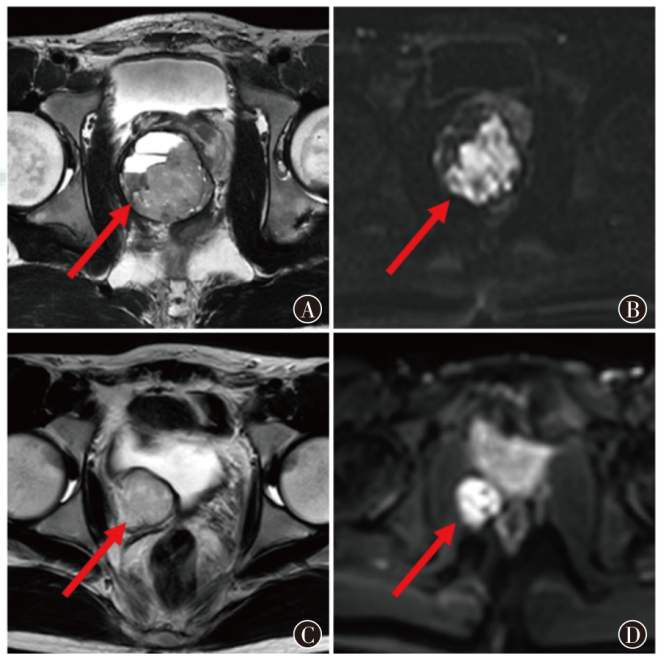

成人前列腺胚胎性横纹肌肉瘤18F-FDG PET/CT显像1例并文献复习

横纹肌肉瘤(RMS)是间叶组织来源的软组织恶性肿瘤,好发于儿童及青少年,原发于成人前列腺者临床上罕见。现报道1例前列腺胚胎性横纹肌肉瘤(ERMS)患者的诊疗经过及18F-FDG PET/CT表现,结合文献探讨前列腺ERMS的影像学特征及诊疗难点,分析PET/CT在肿瘤分期及随访中的价值,以提高对该类疾病的认识。